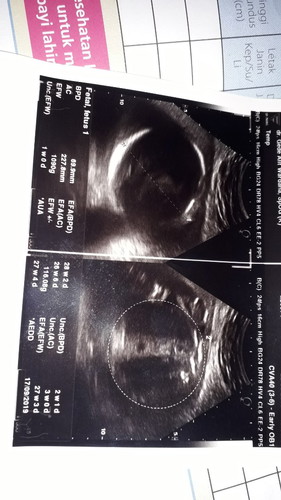

Assalamualaikum bunda.. mau tanya, kemarenkan usg nih, terus kata dokternya anak ku JK nya laki2, tapi koq pas lihat hasil print out usgnya ada kek tanda/simbol yg menunjukkan kalo sepertinya JK baby aku pr... yg bener yg mana yah bun??